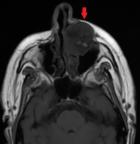

Figure 4: axial T1-weighted image showing a hyporintense lesion of the left maxilla (red arrow)

Diagnostic assessment: a contrast-enhanced facial CT scan showed a well-limited, rounded, expansive intraosseous bony lesion of the left maxillary bone (Figure 1, Figure 2). The process has a trabeculated, sunburst appearance, blowing away the bony cortices, which show very small interruptions in places, there was no periosteal reaction. MRI of the paranasal sinuses revealed a lesion of the left maxillary bone, which had an overall hypo to intermediate T1 signal intensity and a high T2 signal intensity with a marked enhancement after intravenous gadolinium injection (Figure 3, Figure 4, Figure 5). Within the mass were areas of signal void that corresponded to the trabeculae seen in the CT study. Intraorbital structures were intact, with no signs of infiltration, compression or displacement. The diagnosis was confirmed by a bone biopsy (Figure 6).

CT scan is the most useful imaging technique because of its excellent characterization of trabecular and cortical detail and shows a well-circumscribed, rounded mass. It assesses extensions, relationships and mass effects in the vicinity of the tumor lesion [9,10]. The lesion has a "honeycomb" appearance, due to bone trabeculations [9]. When injected, the lesion takes on a strong contrast. MRI is the ideal modality to demonstrate mass-effect complications, such as neural impingement and extraosseous extension the signal intensity is somewhat variable, depending largely on the quantity of slow-moving venous blood and the amount of fat content on MRI, the lesion appears hypointense on T1-weighted images, hyperintense on T2-weighted images with intense enhancement after intraveinous gadolinium injection [8,10]. The differential diagnoses for intraosseous cavernous hemangioma include fibrous dysplasia, osteoma, Langerhans cell histiocytosis, dermoid tumor, and multiple myeloma.